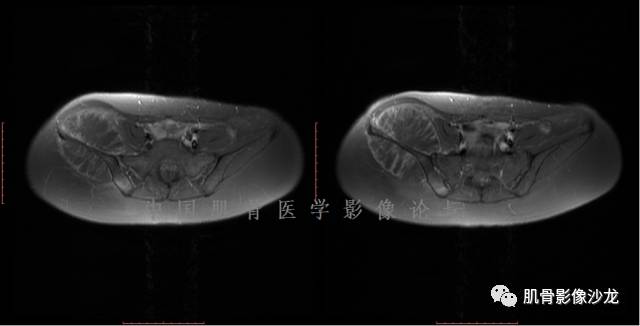

雪舞 :第二例,位于骶骨,有骨质破坏并有软组织肿块,软组织肿块边界清

雪舞: 第二例我们能够看到破坏与软组织肿块不成比例,软组织肿块大,破坏小

雪舞 :第二例挺难的,骨质破坏是溶骨性的,局部皮质中断,软组织肿块外缘光滑

雪舞 : 软骨肉瘤的发病率居原发性恶性骨肿瘤的第三位,其特点是肿瘤内具有软骨基质

雪舞:弓形钙化,钙化比例少于面积的1/3,钙化边缘模糊

雪舞 : 都是软骨肉瘤鉴别于内生软骨瘤有意义的区别点